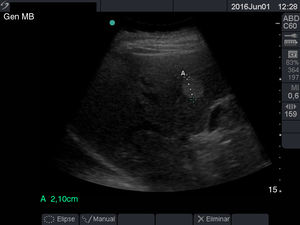

En la ecografía el hígado normal se ve como un órgano homogéneo de color gris mediano, con la misma ecogenicidad o ligeramente más ecogénico que la corteza del riñón derecho, su contorno es liso y el margen inferior acaba en punta anteriormente12, aunque su tamaño presenta una considerable variabilidad, la extensión craneocaudal del lóbulo derecho en la línea medioclavicular suele ser de 12 a 13 cm11 (fig. 1).